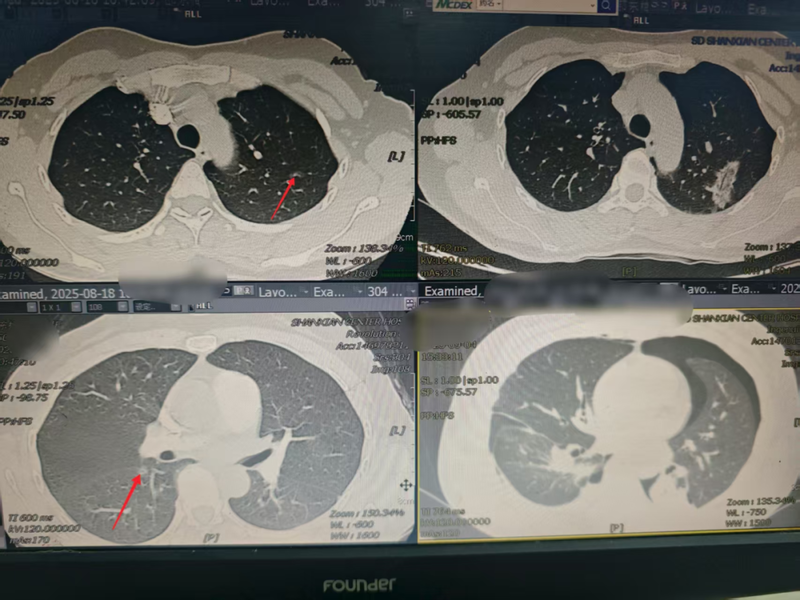

精准施良策,仁心解顽疾——单县中心医院心胸外科成功为双侧肺部多发结节患者行“右肺下叶背段切除+左肺上叶结节微波消融术”

近日,单县中心医院心胸外科成功为一名双侧肺部多发结节患者实施“右肺下叶背段切除+左肺上叶结节微波消融术”。